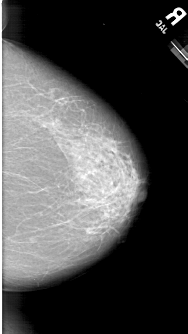

A_1594_1.RIGHT_MLO

RIGHT_CC LINES 6331 PIXELS_PER_LINE 3556 BITS_PER_PIXEL 12 RESOLUTION 43.5 NON_OVERLAY

FILE: A_1594_1.LEFT_CC.OVERLAY

TOTAL_ABNORMALITIES 1

ABNORMALITY 1

LESION_TYPE MASS SHAPE OVAL MARGINS ILL_DEFINED

ASSESSMENT 4

SUBTLETY 5

PATHOLOGY MALIGNANT

TOTAL_OUTLINES 1

BOUNDARY